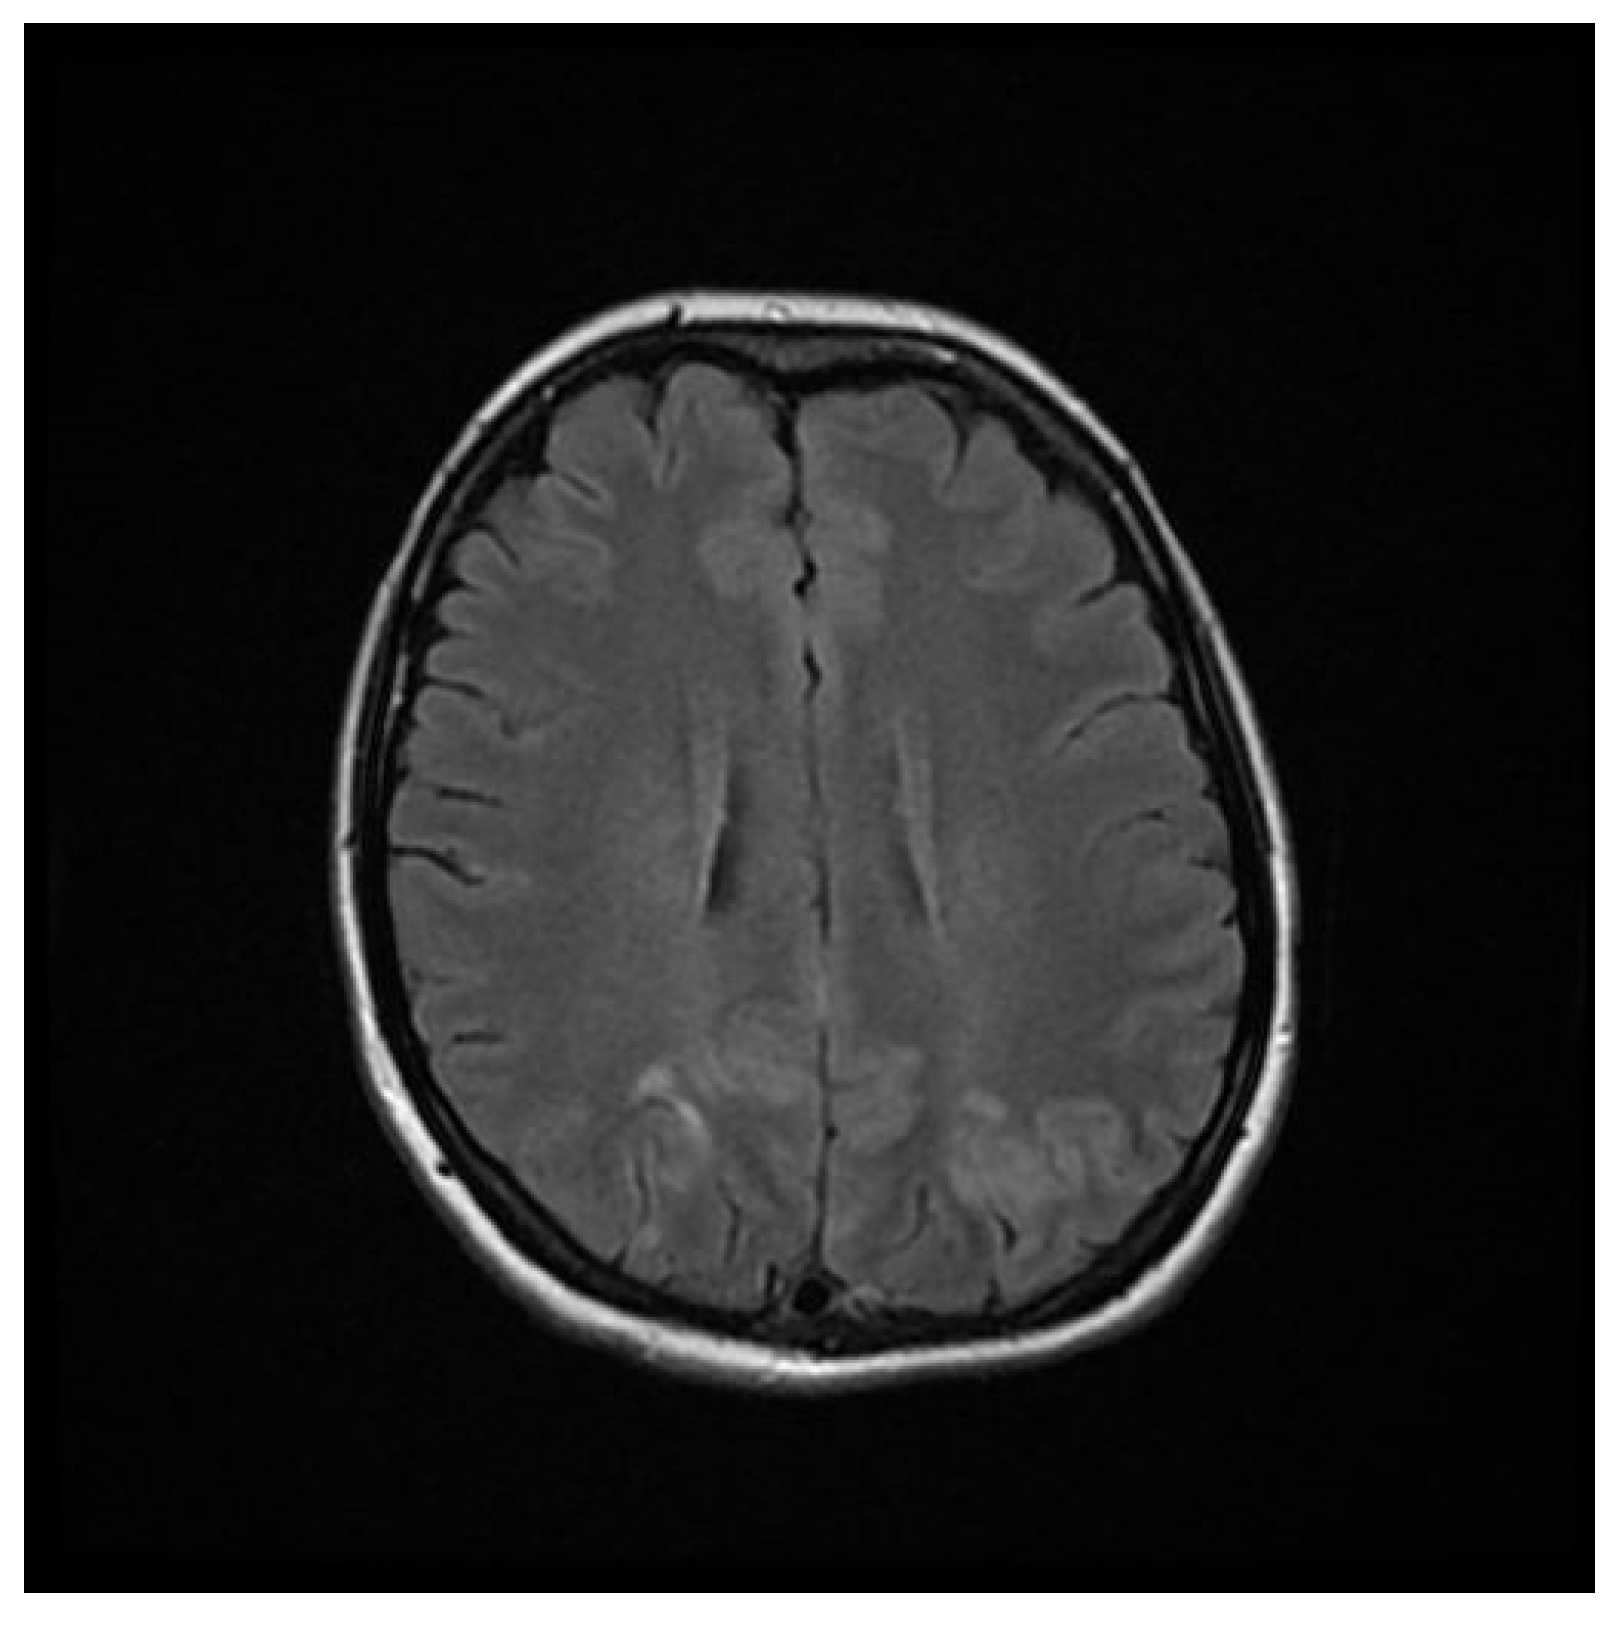

Computed tomography (CT) angiography of the head and CT with contrast were performed and excluded aneurysm, arteriovenous malformation (AVM), dural sinus thrombosis, and tumor. Due to the lack of deviations in the previous tests, an MRI of the head with contrast was performed, in which small areas and hyperintense bands in the T2-weighted image (T2-WI) and Fluid Attenuated Inversion Recovery (FLAIR) were visualized on both sides in the parieto-occipital areas without either diffusion restrictions or contrast enhancement, a typical manifestation of PRES [4], as shown in Figure 1, Figure 2, Figure 3 and Figure 4.

Figure 1. FLAIR MRI sequence of the brain showing hyperintense bands in the parieto-occipital areas on both sides.

Figure 2. FLAIR MRI sequence of the brain.